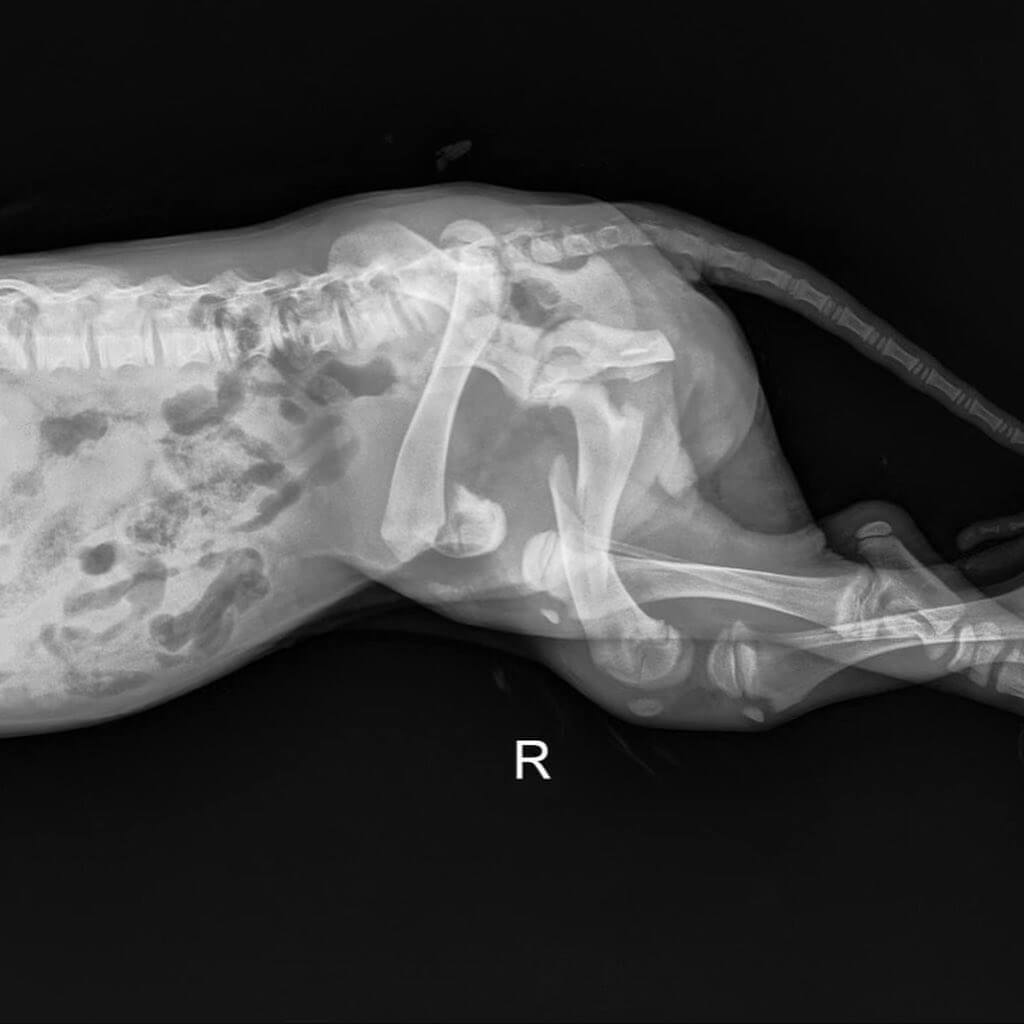

And so Sophie had just been diagnosed with a broken femur and two dislocated hips. She was extremely dehydrated and needed a blood transfusion. Her medical care will cost thousands of dollars.

As to what happened to Sophie is still unknown, but if she had been hit by a car, there likely would have been some outward signs of trauma. The focus, however is now on Sophie and her future.